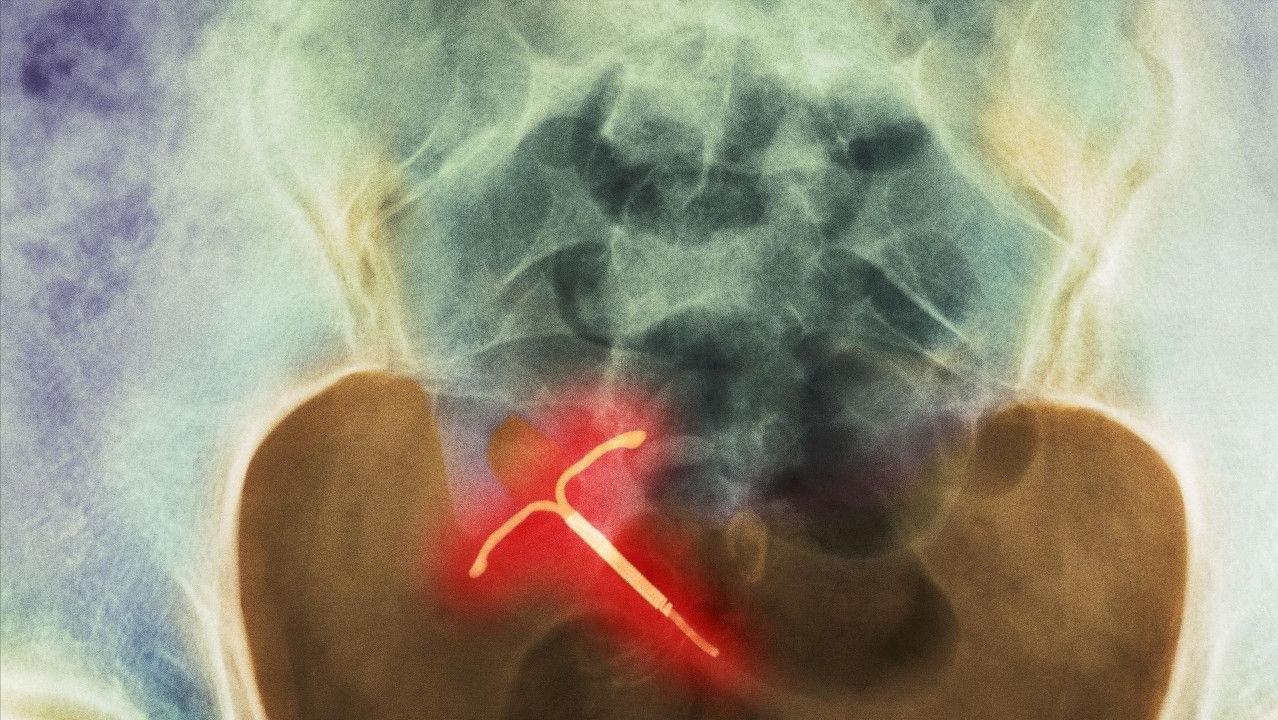

节育环是可以放置在子宫腔内的一种避孕装置,由于其外形如环状,因此得名节育环。它是现如今我国女性用来避孕的最普遍的器械之一。它的工作原理就是通过固定在子宫的特定部位,以此来扰乱受精卵的着床,从而阻止胚胎的发育中间的任意一个步骤,达到避孕效果。

而带药的节育环就是在节育器加上一些药物,孕激素或铜,例如带铜的宫内节育器,可规律释放铜离子,利用铜对精子或受精卵的*伤杀**作用来增强避孕效果。

当然,节育环也并不是一劳永逸的,它是有一定寿命的,到了一定的时间后必须取出。通常来说,金属节育环的使用年限大约是20年,而非金属的使用寿命大概是7~10年,带药的节育环寿命约5~7年。所以,到了一定时间必须到正规医院将其取出来。